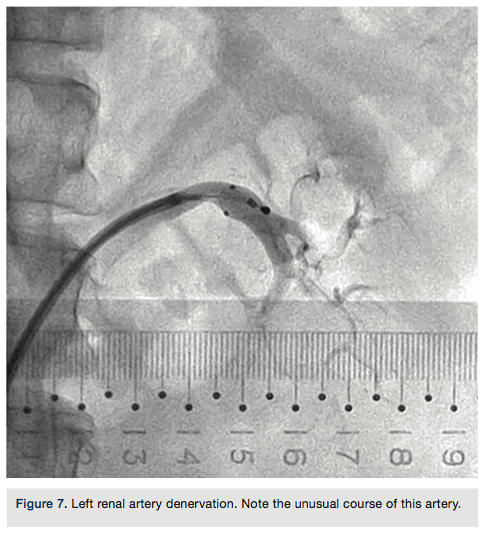

Over the last 4 years, along with my colleagues, I have explored the use of renal denervation for the treatment of hypertension and related comorbidities. As experienced by other radiology colleagues and cardiologists, the preferred or obliged access is the femoral artery. The common experience is that it is not always easy to gain and maintain a vascular target in order to accomplish a planned interventional procedure while using available catheterization equipment.

A good example for use of the Destino is in endovascular renal denervation, following these steps:

- Standard femoral artery puncture.

- 7 French or 8 French standard dilator passage.

- Insertion of Destino Twist with its dilator.

- Destino distal tip arrives at T12 level and dilator is removed, with the standard guide wire having the tip still inside the edge.

- Sheath is flushed and rotating the cursor, the curve is achieved.

- Contrast medium injection allows viewing of the origin of the renal artery.

- Sheath is gently pulled down until the vessel is engaged and angiography is performed.

- Once we have the vessel sizes, the electrode is advanced inside the sheath and with the use of fluoroscopy, slipped inside the artery.

- The action with the cursor increases or releases the curve of the sheath, avoiding dislodgement from the artery.

- The procedure is repeated on the other side. At the end, the sheath is removed and an arterial closure device applied.